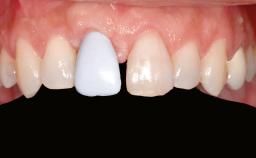

A 45-year-old woman with a completely edentulous maxilla was referred to evaluate the possibility of rehabilitation with an implant-supported prosthesis. This patient was healthy and a non-smoker. She had been wearing a maxillary complete denture opposing a natural mandibular dentition since her twenties. This situation had resulted in progressive resorption of the alveolar ridge, repeatedly creating a need for relining the denture. Twenty years later, despite multiple adaptations and the use of “glues” the denture was unstable and causing the patient psychological and functional discomfort.

Patient's Esthetic Expectations Low Medium High

Esthetic Risk High